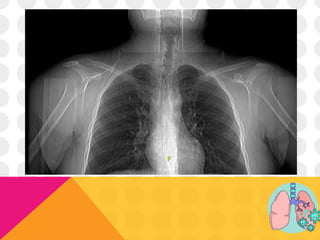

LABS Y TAC SIMPLE DE TÓRAX

Cambios imagenológicos:

TAC SIMPLE DE TÓRAX:

• 90% sensibilidad, 96% especificidad

• Opacidades en vidrio deslustrado con o sin consolidación

• Engrosamiento pleural

• Compromiso pulmonar bilateral